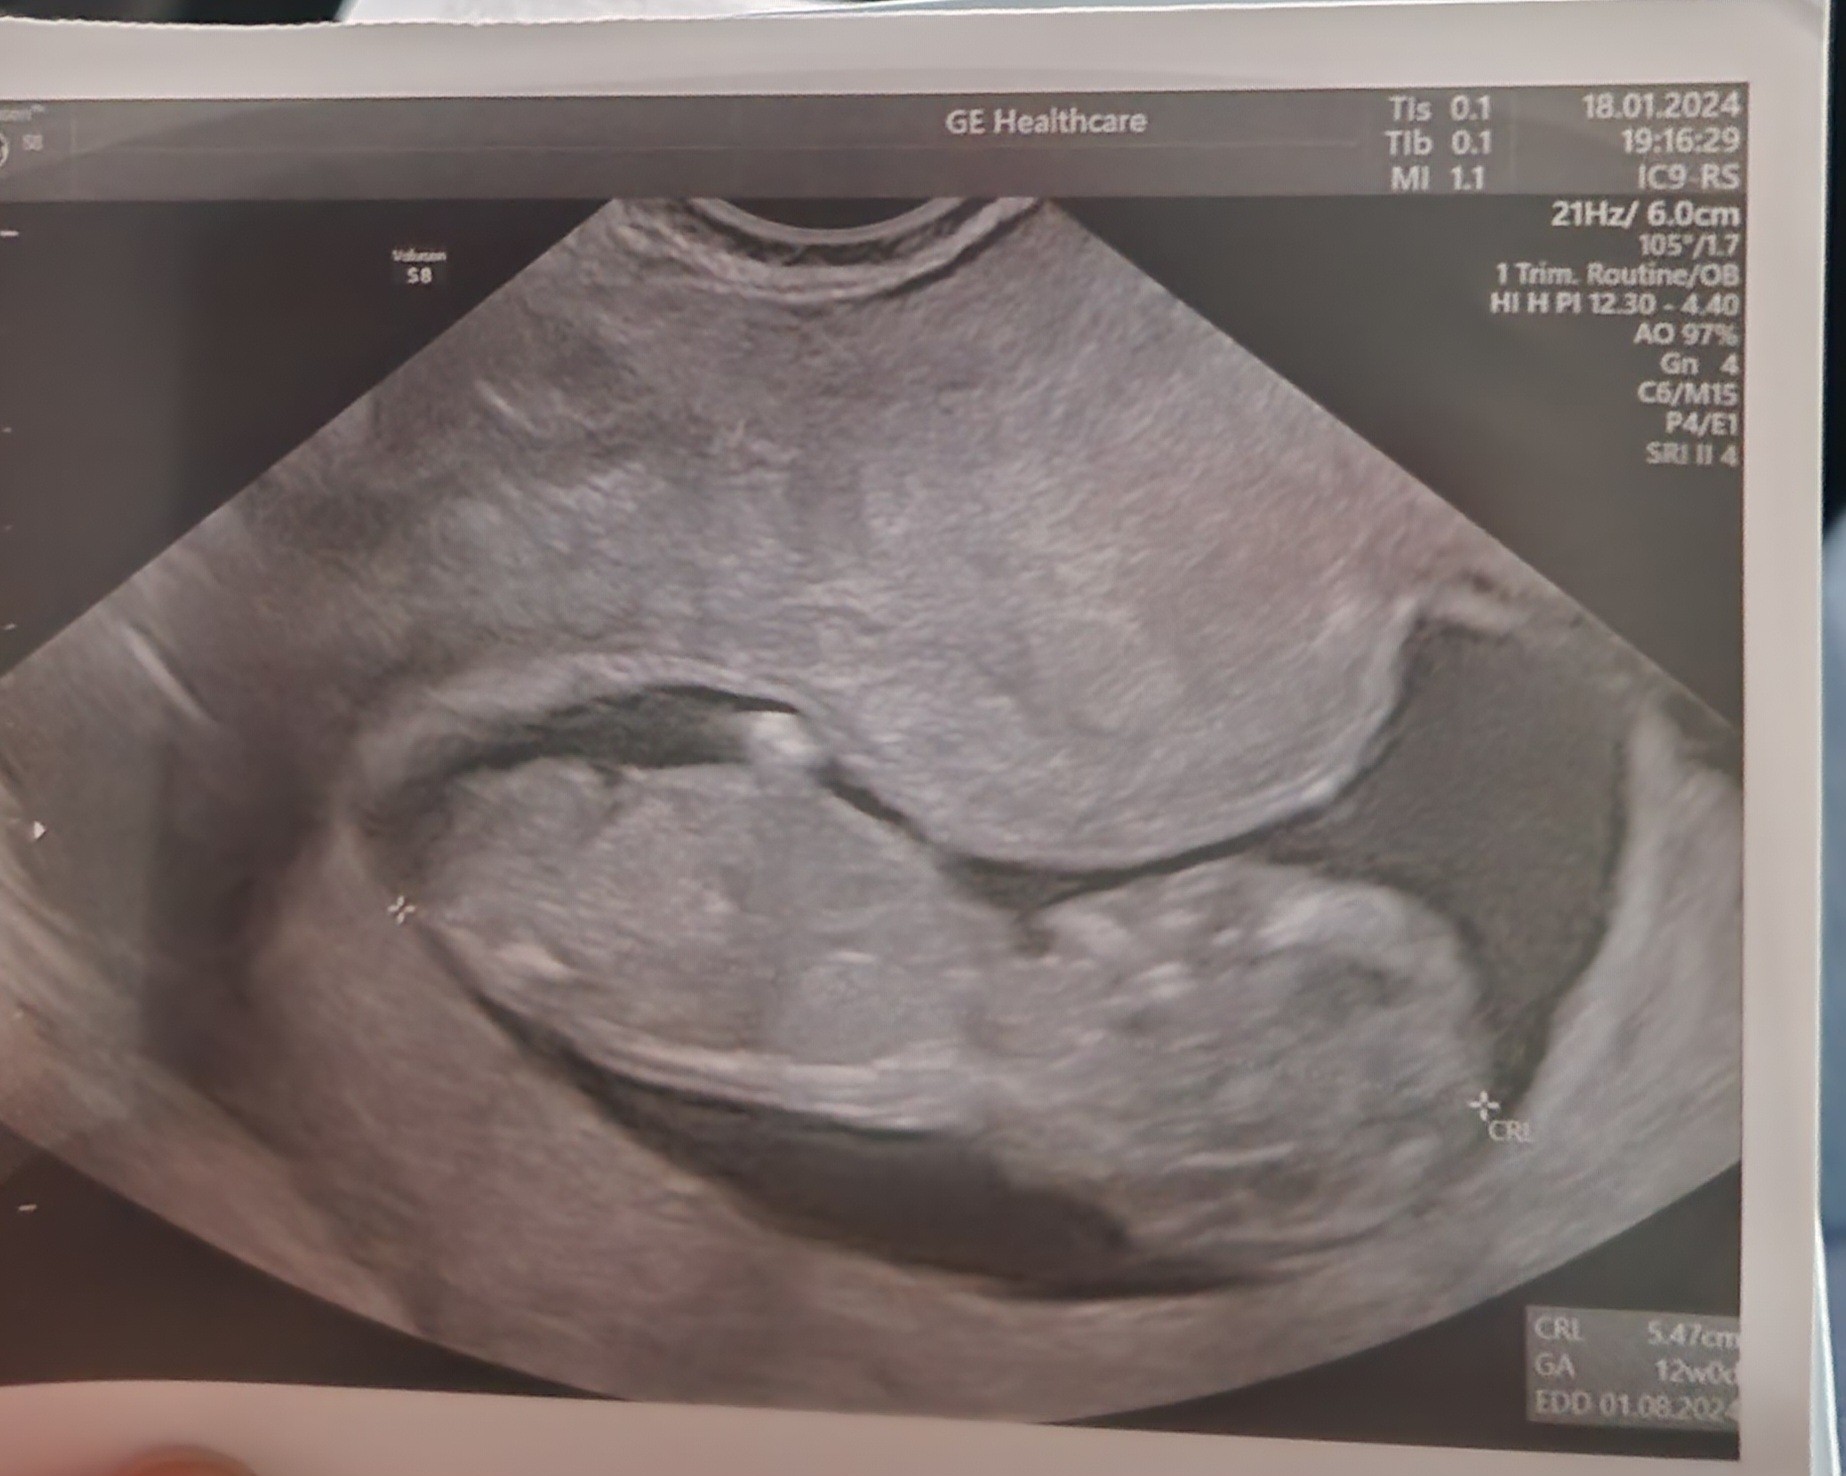

SuperDzidziuś rośnie, serduszko bije. 5,47 cm i wychodzi 12 tydzień, a ja dziś z OM mam 11+0. Pani doktor obejrzała go dokładnie, kręcił się, wiercił, ruszał rączkami. No i powiedziała, że chyba jej na chłopca wygląda choć jeszcze za szybko oceniać![]()

No faktycznie dużego masz już maluszka. Super, bardzo się cieszęDzidziuś rośnie, serduszko bije. 5,47 cm i wychodzi 12 tydzień, a ja dziś z OM mam 11+0. Pani doktor obejrzała go dokładnie, kręcił się, wiercił, ruszał rączkami. No i powiedziała, że chyba jej na chłopca wygląda choć jeszcze za szybko oceniać![]()